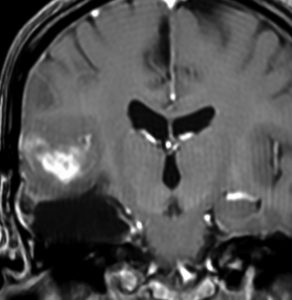

これは4歳の女の子の左の視床にできた乏突起膠腫です。コンピュータガイドの定位脳手術という方法で生検術をしました。病理像はやはり高分化型なのですが,大きくなると困る場所なので,半定位放射線治療を46グレイあてました。MRIの左側は放射線治療前,右側は放射線治療6年後のものです。腫瘍は縮小したままで再燃せず,10年以上経過しますが元気に学校へ行っています。視床下部へ照射が入ったので思春期早発を生じました。